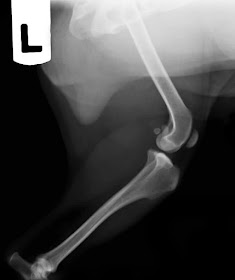

Se trata de una perrita mestiza de unos 3

años y 8 kg con una inestabilidad de su rodilla izquierda, de grado 2-3, que le

ocasiona una cojera sin dolor pero muy evidente.

Veamos el

estudio radiográfico previo a la cirugía:

No es una

cojera especialmente dolorosa, ni hay un alto grado de torsión de los huesos,

además al sedar al paciente y tensar las extremidades la rótula vuelve a su

sitio, pero es evidente que hay un pequeño desplazamiento del cuádriceps sobre

la cresta tibial que provoca la luxación de rótula.